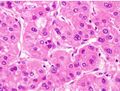

Microscopically, the four architectural and cytological types (patterns) of hepatocellular carcinoma are: fibrolamellar, pseudoglandular (adenoid), pleomorphic (giant cell), and clear cell. In well-differentiated forms, tumor cells resemble hepatocytes, form trabeculae, cords, and nests, and may contain bile pigment in the cytoplasm. In poorly differentiated forms, malignant epithelial cells are discohesive, pleomorphic, anaplastic, and giant. The tumor has a scant stroma and central necrosis because of the poor vascularization.[39] A fifth form – lymphoepithelioma like hepatocellular carcinoma – has also been described.[40][41]

Well-differentiated HCC

Moderately differentiated HCC.

Poorly differentiated HCC